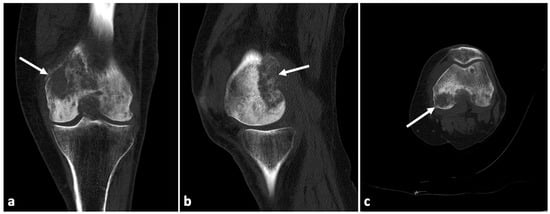

2. Case Presentation